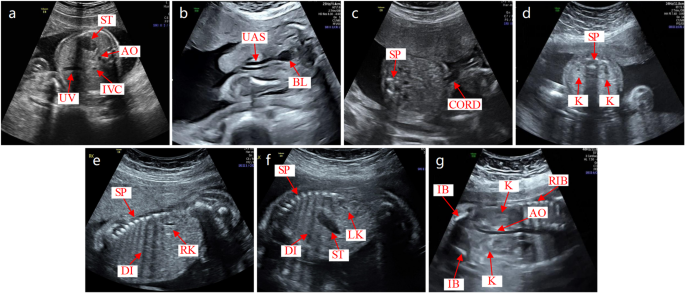

In our examine, we use the detection outcomes of key constructions in fetal stomach ultrasound pictures to establish customary planes. In accordance with medical requirements, we outline the usual fetal stomach ultrasound planes as follows: ACS ought to show the umbilical vein (UV), inferior vena cava (IVC), abdomen bubble (ST), and stomach aorta (AO); UCS ought to clearly present the SP and umbilical CORD; BHS ought to exhibit the bladder (BL) and UAS; BKHS ought to show the kidney (Okay) and SP; LKS ought to present the left kidney (LK), ST, diaphragm (DI), and SP; RKS ought to current the fitting kidney (RK), DI, and SP; BKCS ought to embody the Okay, umbilical artery (IB), AO, and RIB. The precise identification course of is as follows: First, we outline the goal class dictionary P for every customary aircraft as: ACS: [UV, IVC, ST, AO], UCS: [SP, CORD], BHS: [BL, UAS], BKHS: [K, SP], LKS: [LK, ST, DI, SP], RKS: [RK, DI, SP], BKCS: [K, IB, AO, RIB]. Subsequent, based mostly on the detection outcomes which embody confidence rating, class, and bounding field coordinates (x1, y1, x2, y2), we choose the category with the very best confidence because the goal marker. Lastly, by verifying whether or not these predicted targets utterly match the predefined goal listing for the usual aircraft, we verify whether or not the ultrasound picture corresponds to the usual aircraft and output the variety of detected objects and the class of the FAUSP. The design of FAUSP-NET successfully overcomes the challenges of time-consuming and error-prone identification processes that may result in non-standard choices. It doesn’t depend on in depth pre-training with massive datasets however performs inference instantly from detection outcomes. This strategy not solely considerably reduces coaching time and reminiscence necessities but additionally accelerates the implementation of FAUSP-NET, aligning the inference course of intently with medical judgment workflows. This makes FAUSP-NET extra appropriate for medical functions and supplies higher interpretability and intuitiveness.